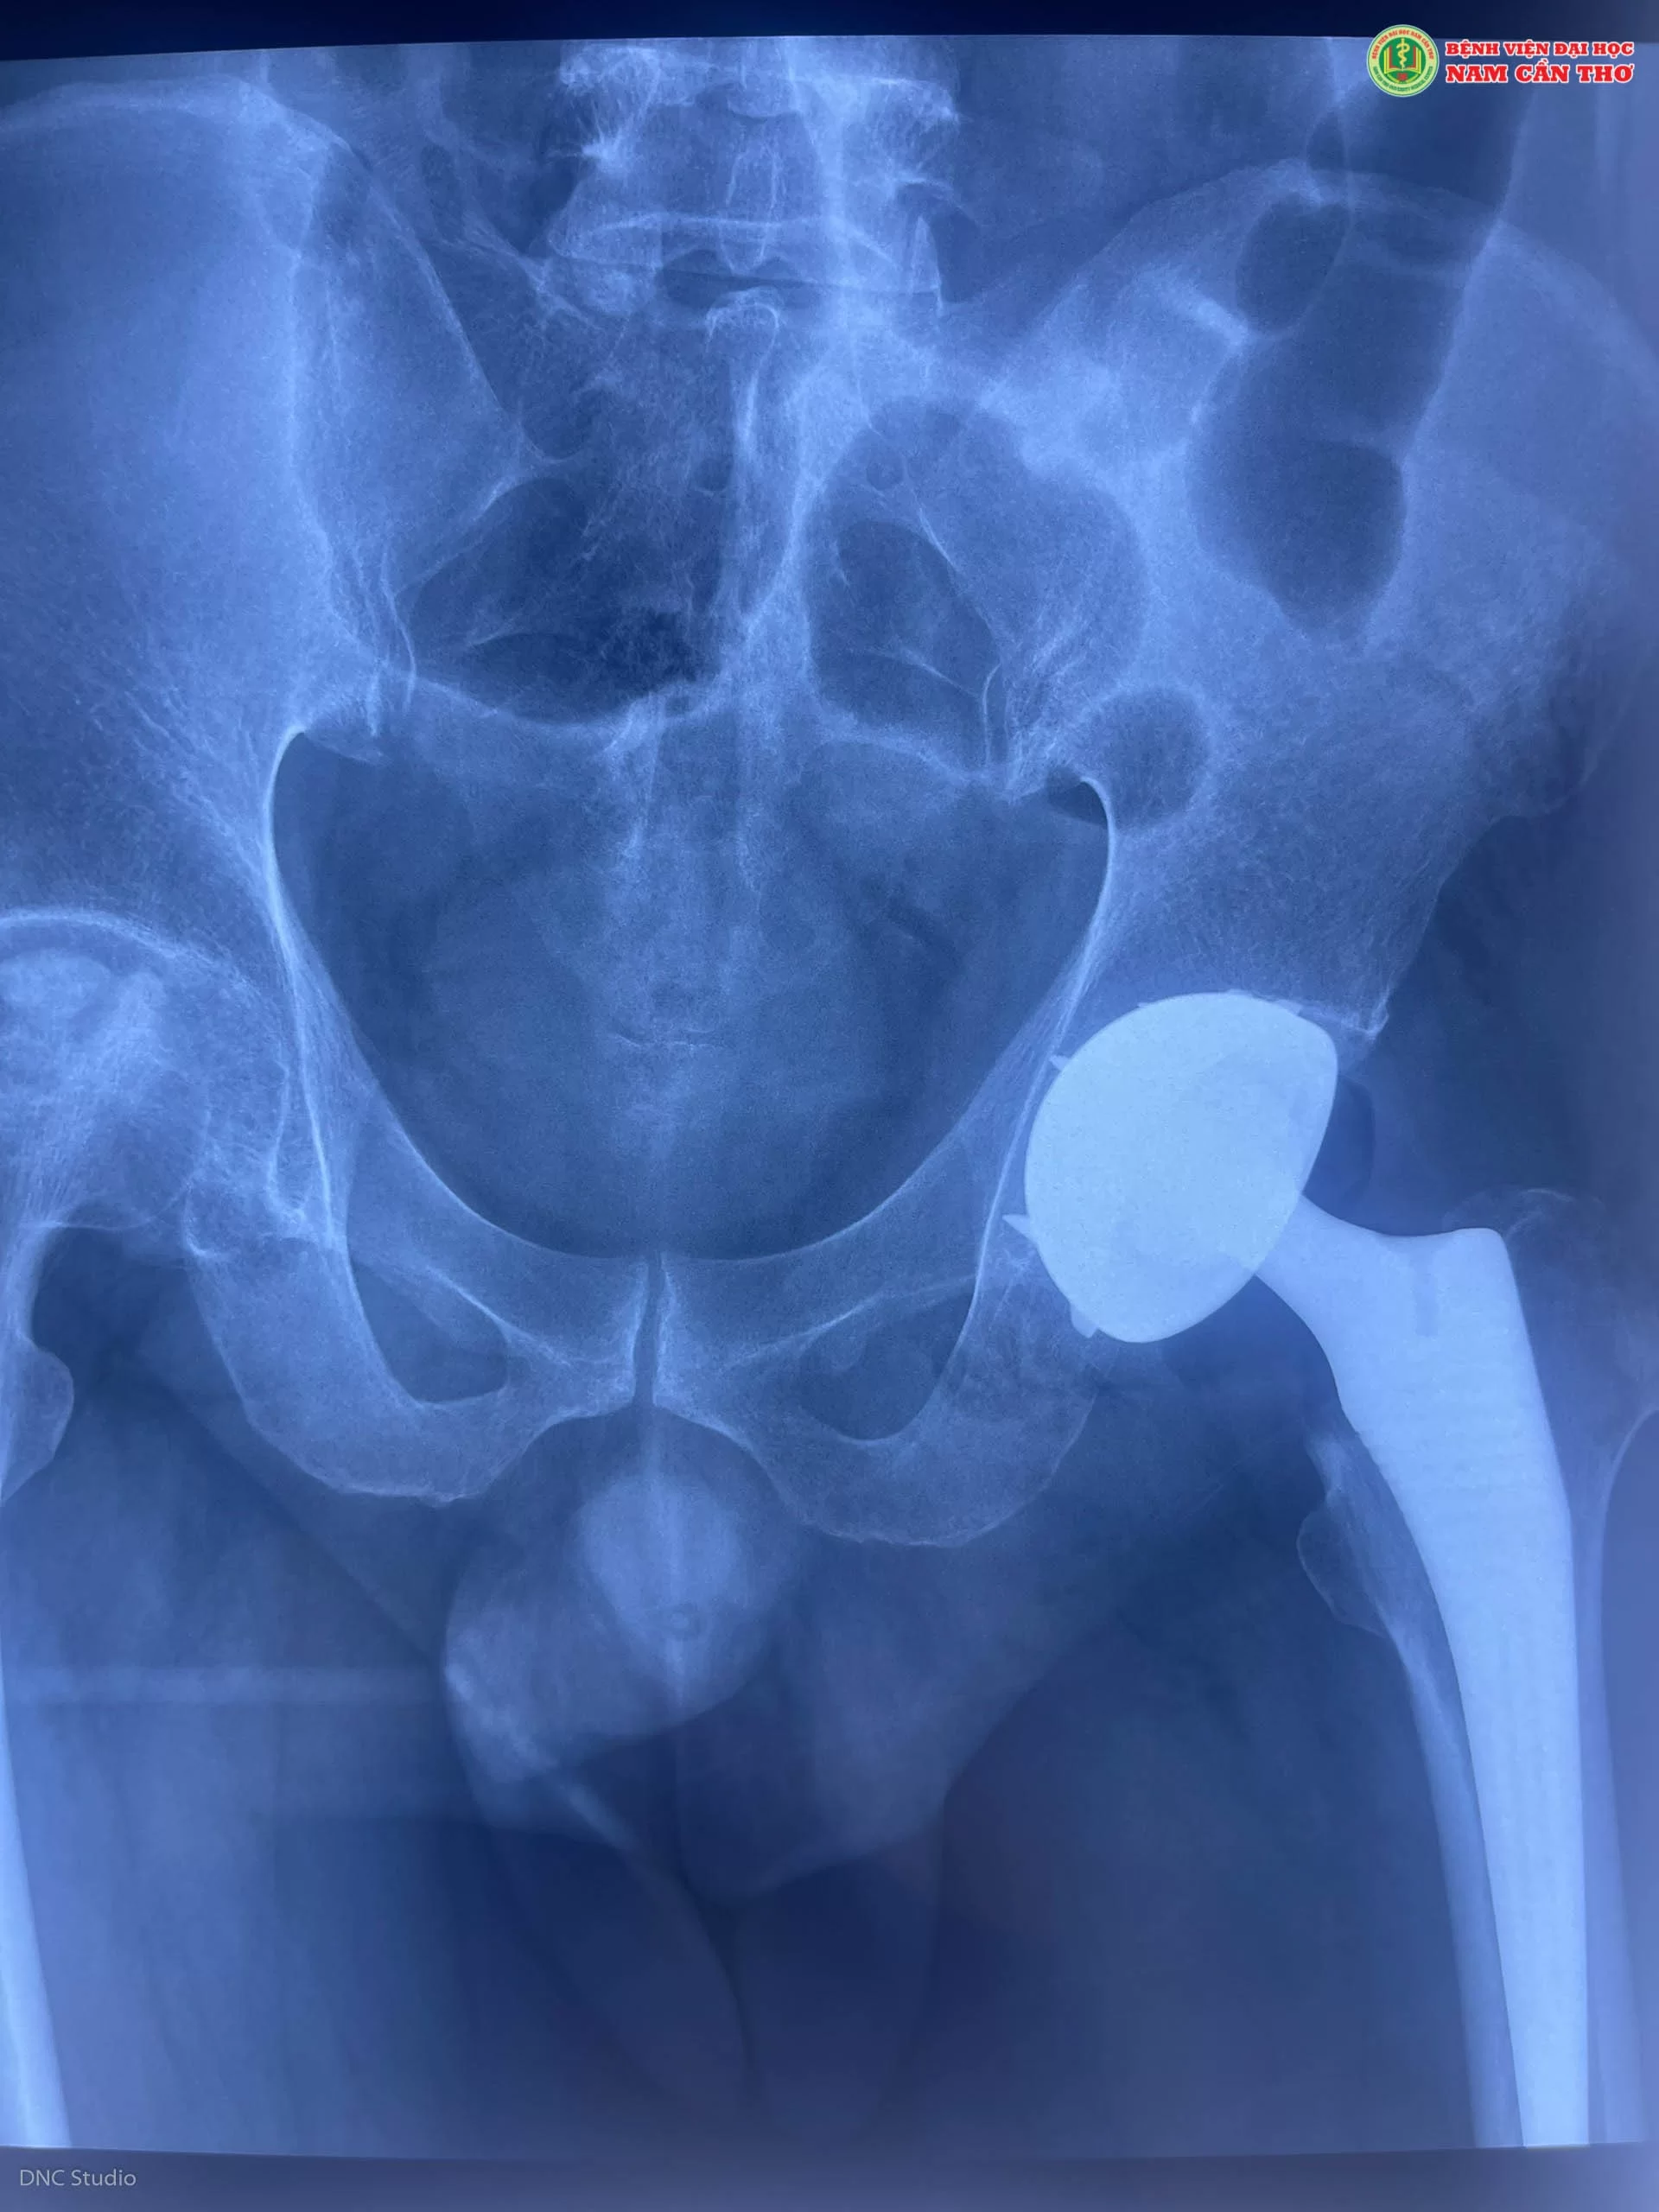

Kết quả sau khi phẫu thuật thay khớp háng (Ảnh DNC Studio)

Sau 4 ngày phẫu thuật thay khớp háng, anh K tập đi lại xung quanh phòng với sự hỗ trợ của khung tập đi. Cùng với đó là sự hướng dẫn trực tiếp từ bác sĩ chuyên môn trong việc tập vật lý trị liệu sau phẫu thuật. Đối với phẫu thuật thay khớp háng, khi hết đau người bệnh có thể nhanh chóng trở về cuộc sống sinh hoạt bình thường.